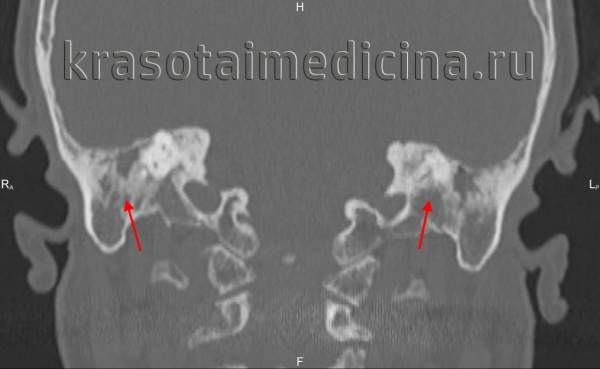

КТ при хроническом отомастоидите с эрозиями слуховых косточек

б) Визуализация:

• Костная КТ:

о Необходимо оценить анатомию слуховых косточек:

- Аксиальная КТ/эпитимпанум: «мороженое в рожке» (передняя часть или «мороженое» = головка молоточка; задняя часть или «рожок»=тело наковальни/короткий отросток)

- Аксиальная КТ/мезотимпанум: «две параллельные линии» [передняя линия = сухожилие мышцы, напрягающей барабанную перепонку, идущее к шейке молоточка; задняя линия = лентикулярный отросток наковальни, наковальне-стременной сустав (НСС) и головка стремечка]

- Корональная КТ на уровне длинного отростка наковальни: «прямой угол» (вертикально ориентированный длинный отросток наковальни, горизонтально ориентированный лентикулярный отросток)

о Аксиальная КТ в костном окне:

- Частичное отсутствие одной из «двух параллельных линий» (задней)

о НСС может быть замещен фиброзной тканью:

На аксиальной КТ НСС выглядит расширенным

- Также возникают эрозии «рожка» (тело/короткий отросток наковальни)

о Корональная КТ в костном окне:

- Длинный отросток наковальни чаще всего отсутствует:

Вертикальный сегмент «прямого угла» отсутствует

- Часто обнаруживается втяжение барабанной перепонки

о Типично снижение пневматизации сосцевидного отростка

(Слева) На рисунке (поперечный срез) левой височной кости показаны поствоспалительные эрозии длинного отростка наковальни и основания стремечка. Обратите внимание на склероз барабанной перепонки и слуховых косточек.

(Справа) При корональной КТ в костном окне определяется втяжение утолщенной барабанной перегородки наряду с деминерализацией длинного отростка наковальни. Уплотненные мягкие ткани в среднем ухе обусловлены сопутствующим воспалительным дебрисом.